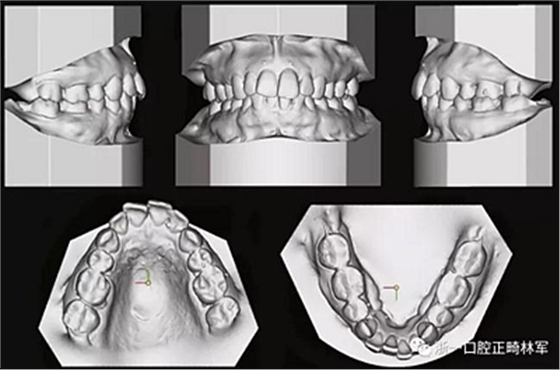

患者曾行正畸治療,現(xiàn)覺(jué)笑容不美觀前來(lái)就診?;颊哒嬗^及側(cè)貌示下頜發(fā)育不足,偏高角,唇閉合不全。上下頜中線(xiàn)齊。覆合、覆蓋4毫米。磨牙關(guān)系及尖牙關(guān)系II類(lèi)。上頜擁擠度4mm,下頜擁擠度6mm。4顆第一前磨牙在第一次正畸治療時(shí)已拔除。上下牙弓呈尖圓型,牙弓狹窄。

患者側(cè)貌改善,下唇唇肌緊張消失,上下唇可自然閉合。磨牙及尖牙關(guān)系糾正至I類(lèi),覆合覆蓋正常。上下頜弓型糾正至卵圓形,牙弓寬度增加。頭影測(cè)量分析示SNA角81.8°,ANB角3°。頭影測(cè)量重疊圖示下頜骨向后旋轉(zhuǎn),垂直面高度略有增加。